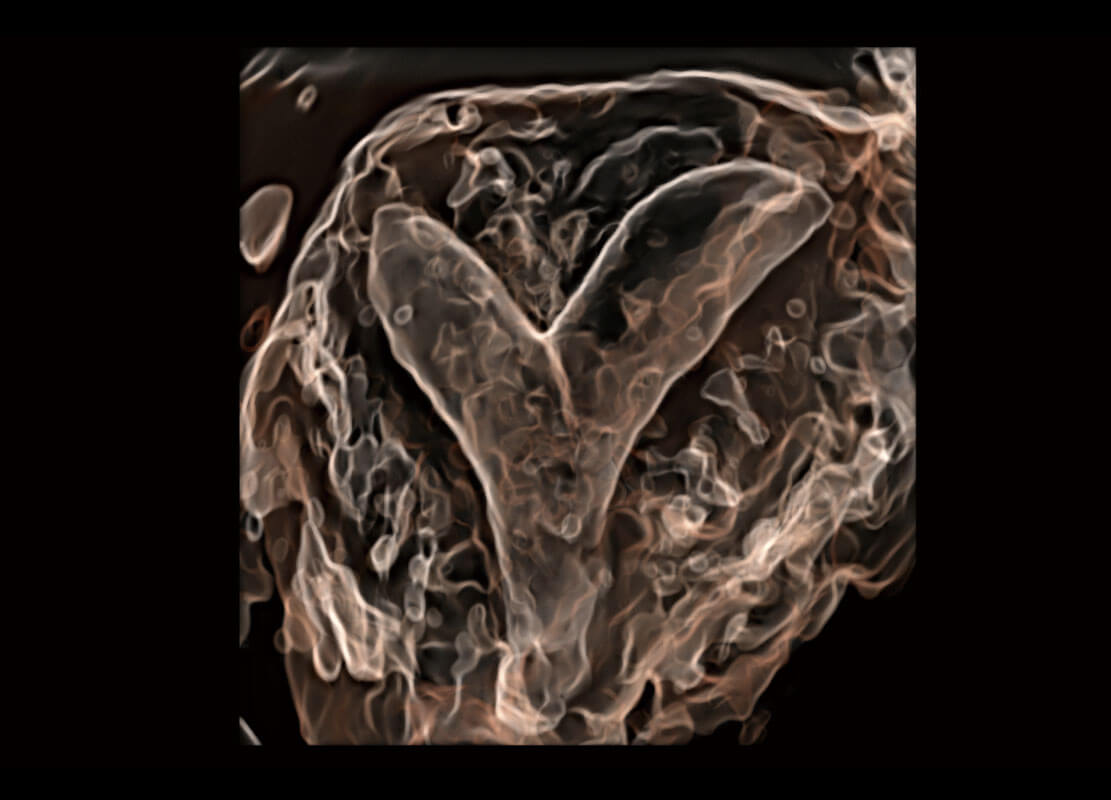

腔内三维-光影成像

P60为盆底超声检查提供应用方案,多种腔内及腹部容积探头提供从二维、三维到四维的优异图像品质,实时快速三维容积数据获取,专业的测量工具包等人性化设计,为超声医生诊断提供有力保障。